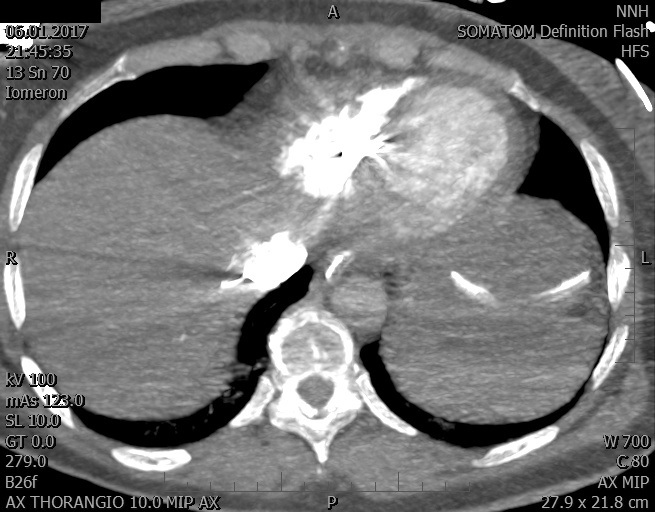

Video 2 - Echokardiograficky byla zjištěna těžká dysfunkce dilatační levé komory s nezvětšenou pravou komorou.Pro nejasnou příčinu zástavy jsme provedli i vyšetření výpočetní tomografií (CT), které vyloučilo plicní embolizaci (série 1 - soubory na konci článku). V den přijetí při přetrvávající oběhové nestabilitě byla nemocná opakovaně defibrilována pro fibrilaci komor se stabilizací rytmu po podání amiodaronu a mesocainu. Dle hemodynamických měření se jednalo o těžký kombinovaný šok. Vstupní laboratorní vyšetření bylo bez větších pozoruhodností. Posléze jsme doplnili anamnézu od příbuzných a zjistili, že pacientka užila do dvou hodin před srdeční zástavou první tabletu amoxicilinu na lehký respirační infekt. Při nevýtěžnosti vstupních vyšetření a nových anamnestických informacích jsme doplnili 14 hodin po kolapsu vyšetření koncentrace tryptázy v séru, která byla extrémně zvýšena (tabulka 2), což nás vedlo k podezření na anafylaxi.